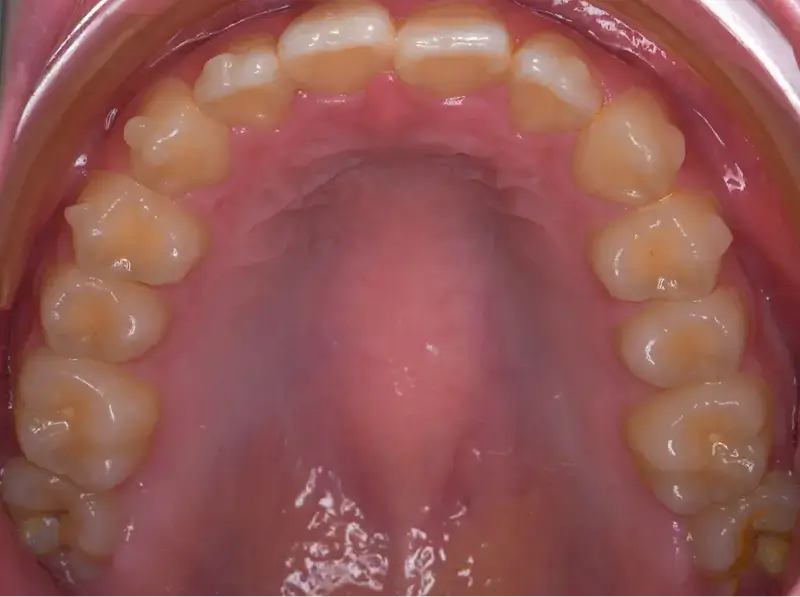

兒童早期矯正,又稱為「預防性矯正」或「第一階段矯正」,指的是在孩子乳牙或混合牙期(約7~10歲)時,就針對牙齒排列、咬合不正、牙弓發育等問題提前介入的矯正治療。 目的不只是「把牙齒排整齊」,更重要的是引導上下顎正常發育,減少未來拔牙、正顎手術的機率,讓恆牙有足夠空間健康萌發。

透過早期擴大牙弓、改善空間,能降低日後因擁擠而必須拔牙的情況。

增加牙弓空間幫助換牙

減少拔牙開刀機率